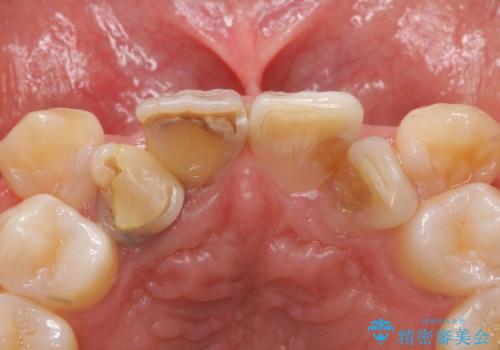

- 神経が死んでいる前歯2本(右上21)をセラミッククラウンでかぶせたいとご希望され、来院された患者様です。

歯並びにより、そのままだときれいに被せ物をいれられない状態でした。

補綴前矯正としてマウスピース矯正(インビザライン)を行った後、セラミッククラウンによる補綴治療を行いました。

右上21:ジルコニアクラウン スペシャル